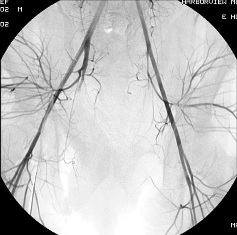

女性盆腔血管实物图

女性盆腔血管分布图

女性盆腔血管分布主要:是膀胱、生殖器官和直肠、是植物神经功能紊乱、事站立工作、子宫后位、长期便秘、早婚早育、孕产频繁的人,以及患有盆腔炎、附件炎、子宫内膜炎等炎症时,静脉血流量增多,盆腔静脉压力增高,影响静脉回流,也容易导致充血。 一般女性在性兴奋时,大量血液涌入盆腔组织,形成充血状态。如果未能达到性高潮,则盆腔充血状态消退很缓慢,会出现下腹坠胀、酸痛等不适。